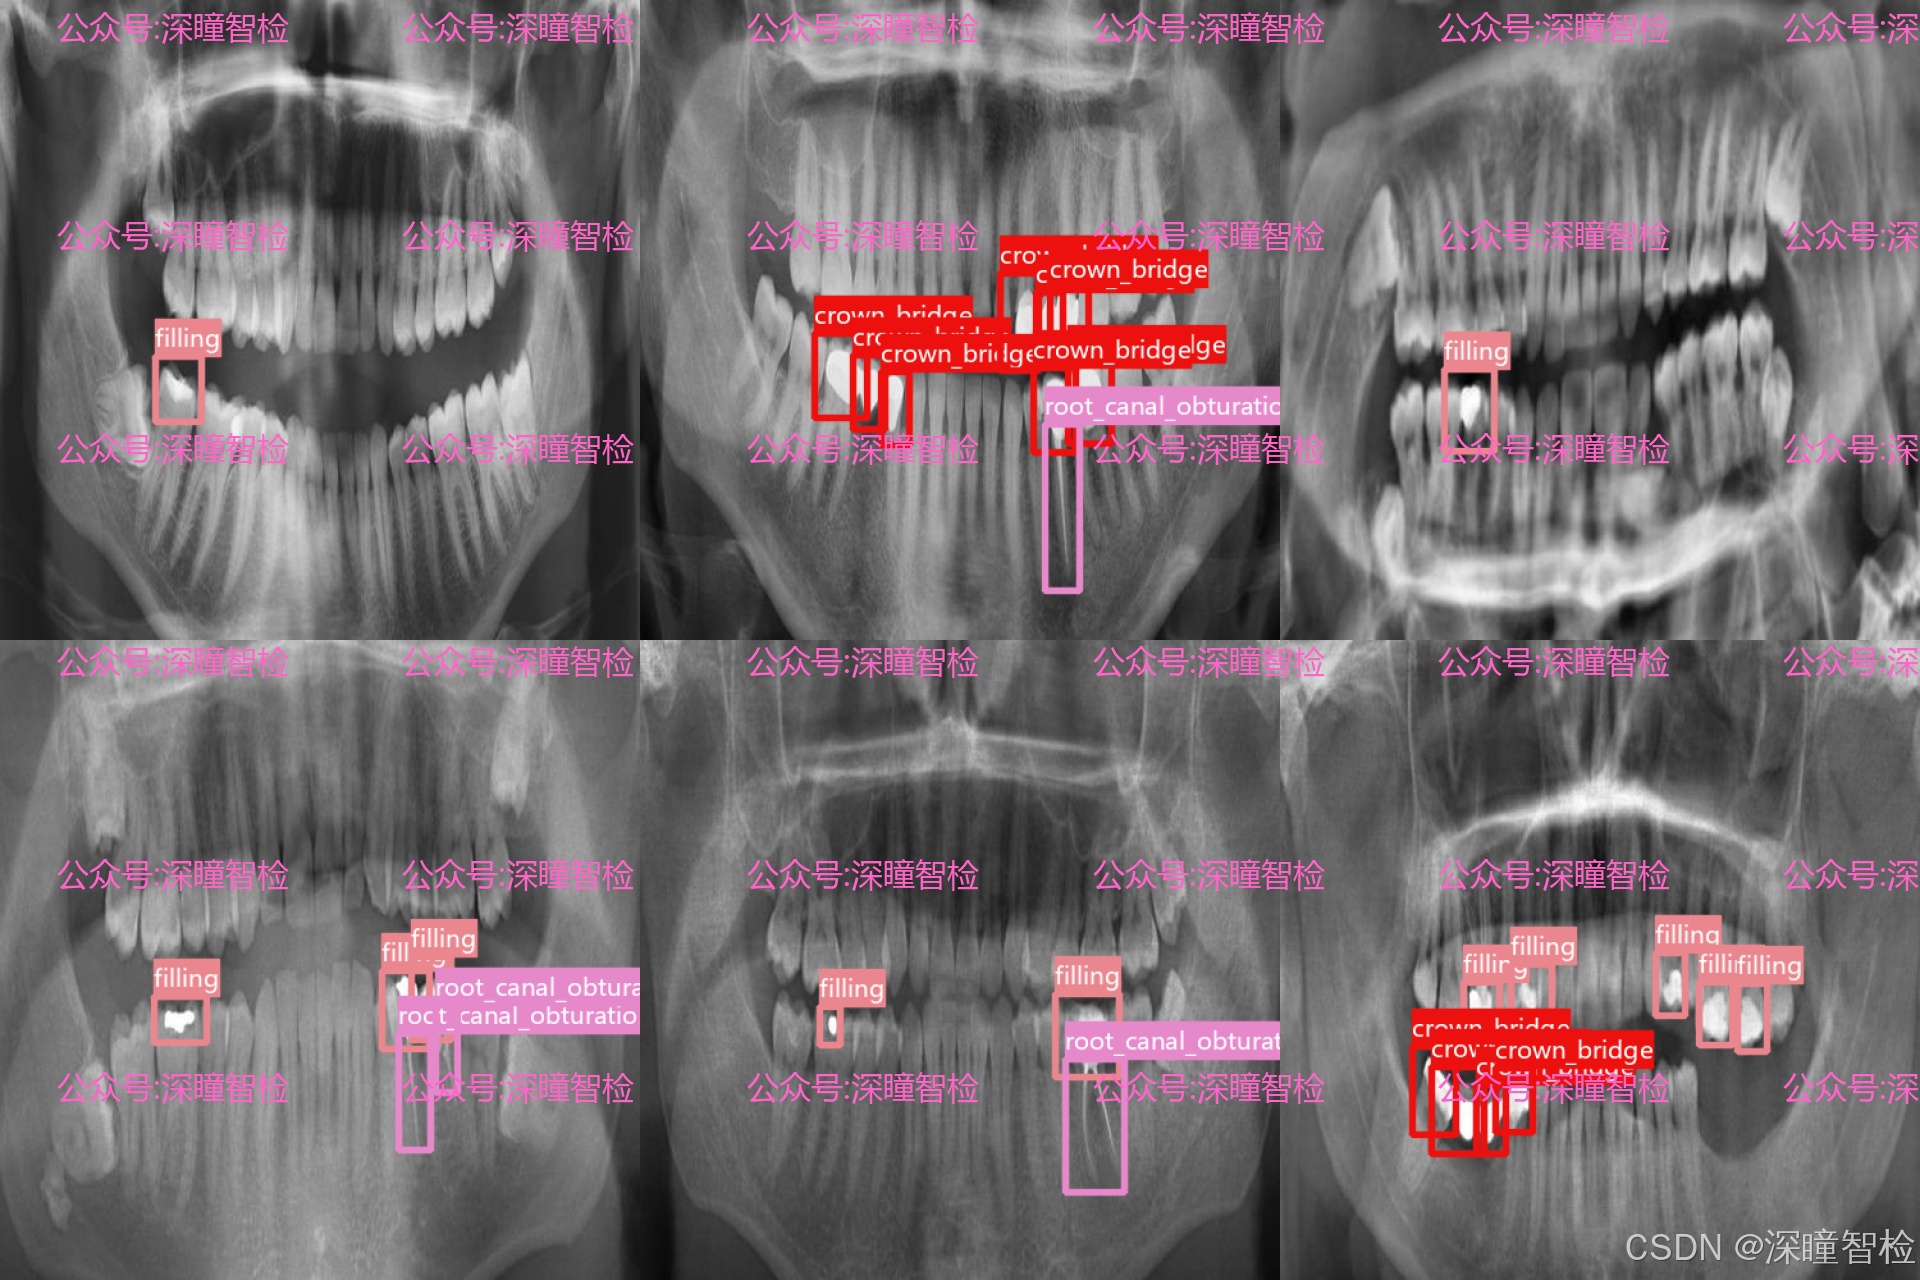

数据集围绕临床中常见的牙体修复及治疗后表现,定义了 4 类关键检测目标:

- • 充填物(filling):包含各类树脂、银汞等补牙材料影像,对应龋齿等牙体缺损的基础修复方式。

- • 冠桥修复体(crown_bridge):覆盖单冠、连冠及固定桥等修复体影像,对应牙体大面积缺损或缺失的修复方案。

- • 种植牙根(implant):包含植入颌骨内的种植体影像,对应牙列缺失的种植修复方式。

- • 根管充填物(root_canal_obturation):包含根管治疗后填充的牙胶尖等材料影像,对应牙髓病与根尖周病的治疗后表现。

每一类标注均由具备口腔医学背景的专业人员完成,通过多人交叉审核机制确保标注的准确性与一致性,为模型学习提供了高可信度的监督信号。